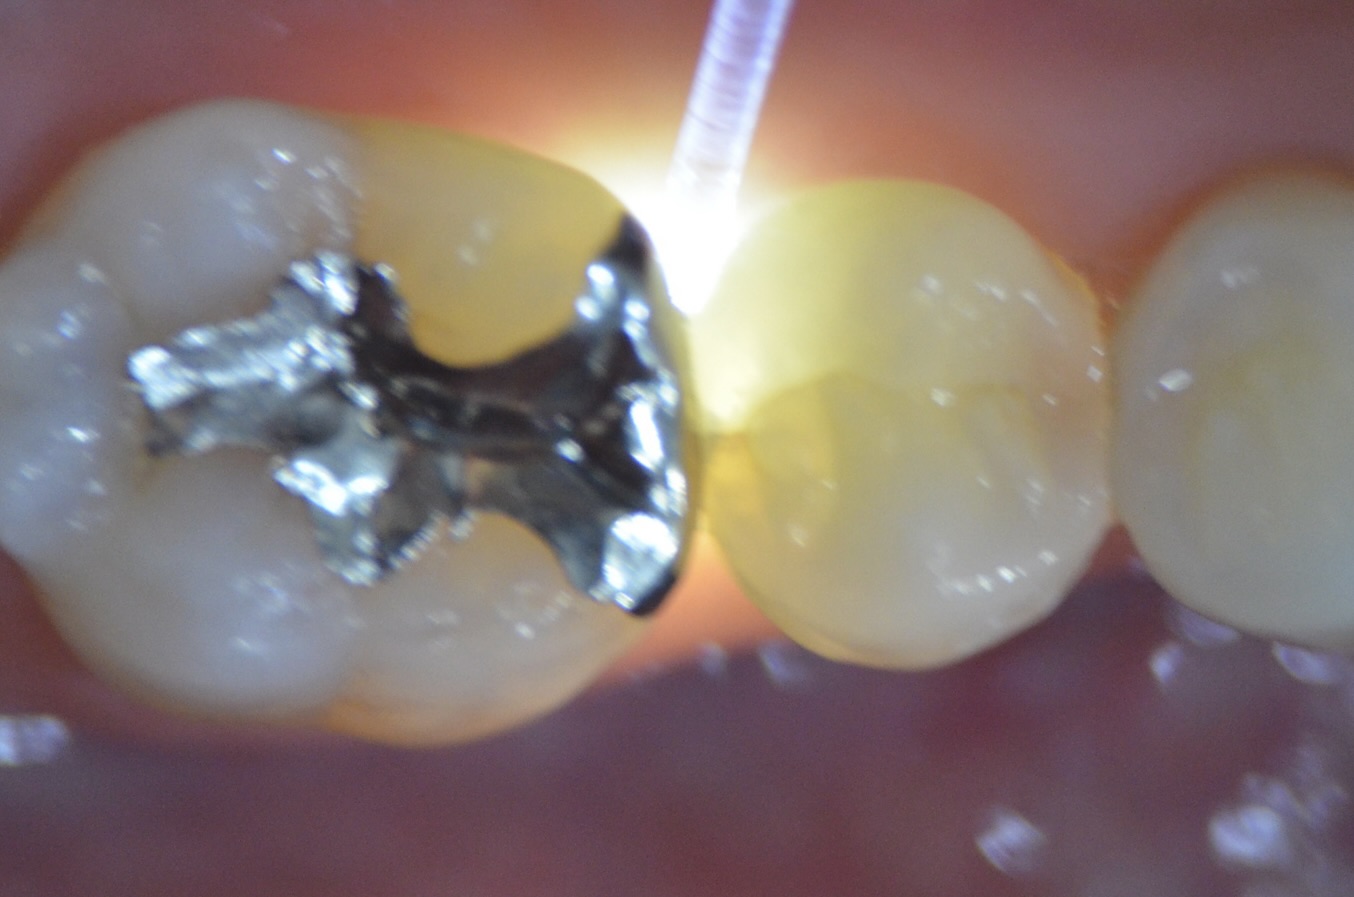

透照診 右下5番遠心

暗がりの中、光を当てると虫歯の微分が黒く見えます。 -

透照診 右下7番近心